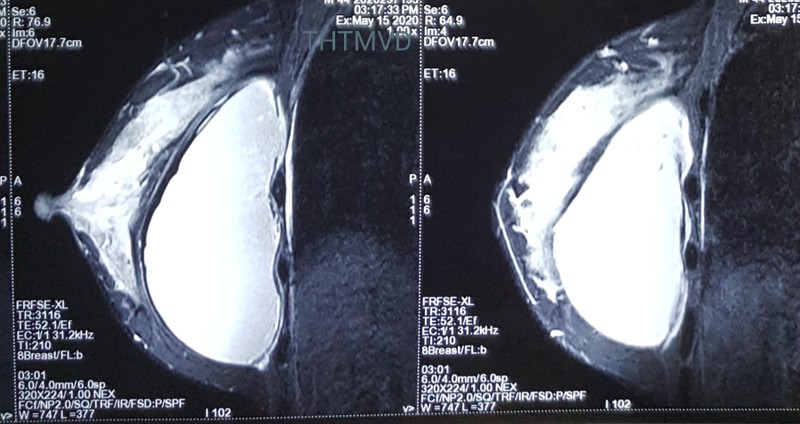

PGS.TS. Nguyễn Hồng Hà - Trưởng khoa Phẫu thuật Tạo hình Thẩm mỹ - cho biết: Người bệnh đến viện trong tình trạng lo lắng, bất an, thăm khám kỹ nhận thấy bề mặt túi ngực nhấp nhô không đều kết hợp. Hỏi kỹ tiền sử cho thấy chị V. đã được đặt túi nhám to giọt nước. Nhận thấy có đề bất thường, các bác sĩ đã chỉ định chụp cộng hưởng từ bằng máy 3.0 Tesla. Đây phương tiện chuyên dụng hiện đại nhất trong chẩn đoán các bệnh lý tuyến vú hiện nay. Kết quả chụp MRI cho thấy hình ảnh túi ngực đã vỡ từ trước mà chị V. không biết. Chính vì thế, chị V. đã được chỉ phẫu thuật ngay lập tức.

Hình ảnh túi ngực của bệnh nhân (Ảnh: Bệnh viện Hữu nghị Việt Đức)